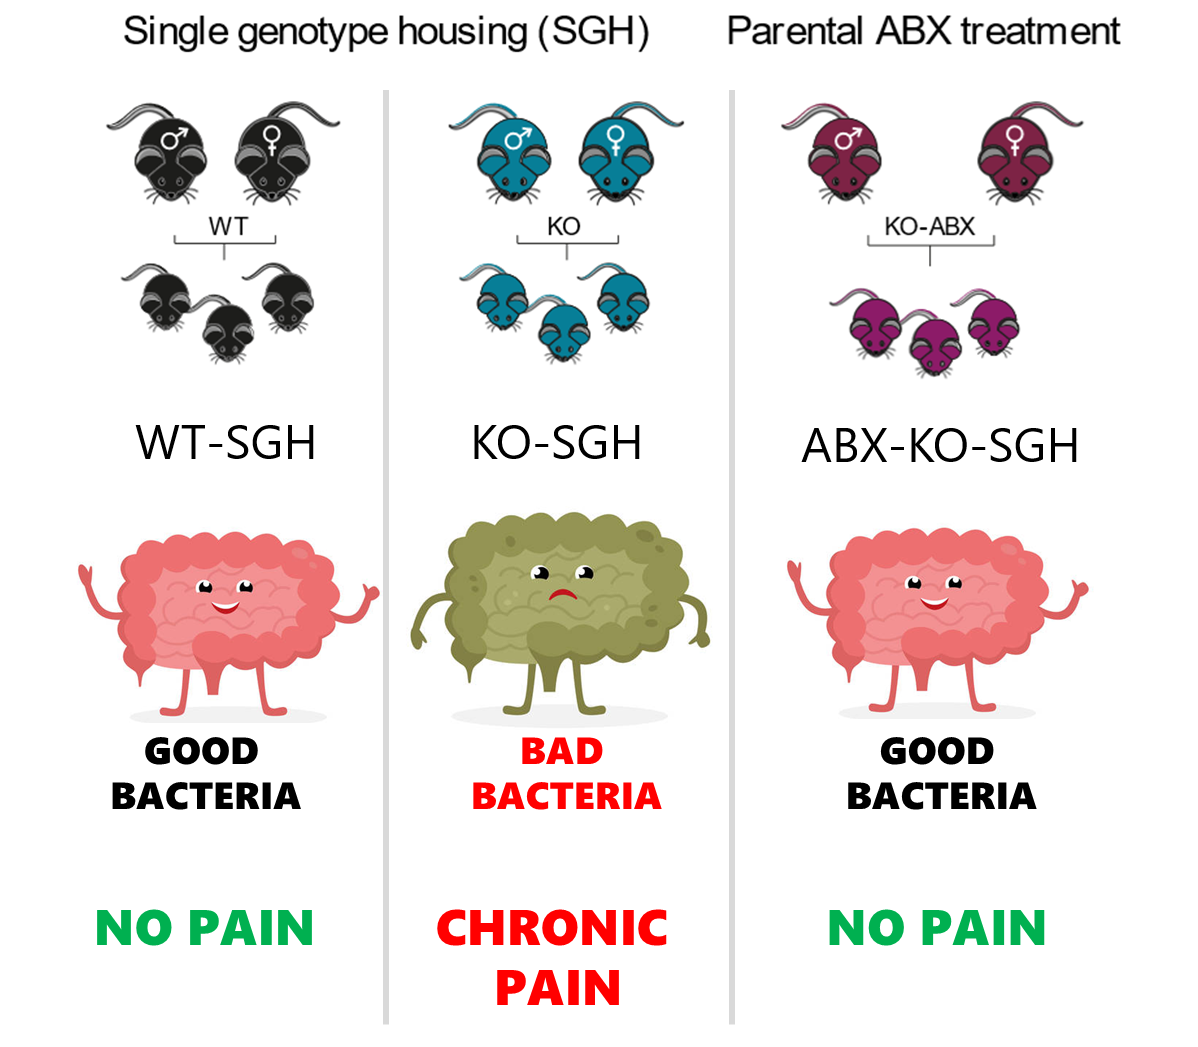

Chronic pain starts from the gut

Alterations in gut microbiota composition promotes chronic somatic pain in Myosin1a-deficient male mice.